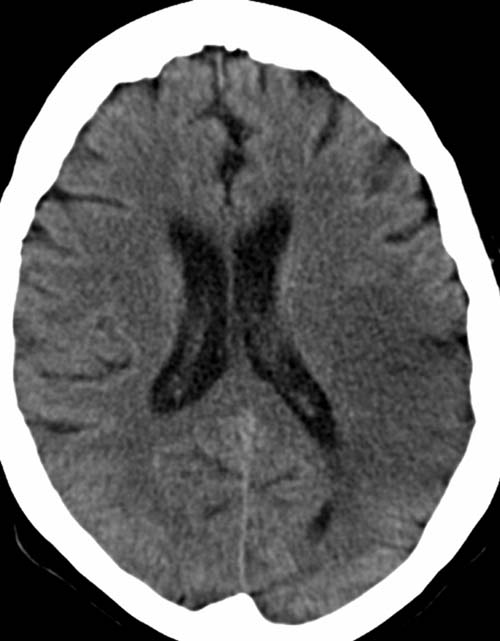

CCT nativ (ohne Kontrastmittel).

Hypodense Darstellung des hinteren Mediastromgebietes links. Konturunschärfe der Rindenmarkgrenze links.

Subakuter Mediateilinfarkt links (12-48h).